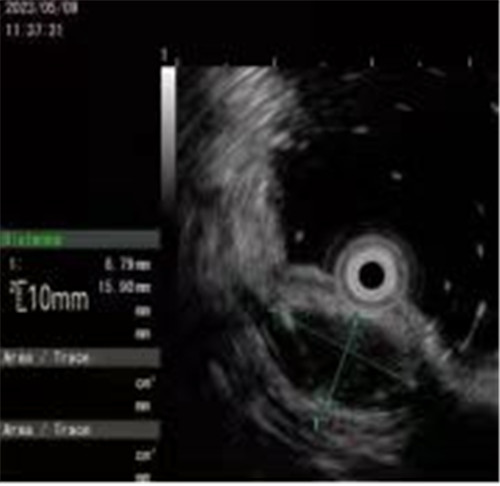

近期病例之一,圖片依次為:胃鏡、超聲胃鏡、ESE術(shù)中、術(shù)后、切下病變。

內(nèi)鏡超聲小探頭可用于探查消化道管壁腫物。消化道管壁分為4層,從內(nèi)到外依次為粘膜層、粘膜下層、肌層、漿膜層,不同分層內(nèi)的病變性質(zhì)各異。

內(nèi)鏡超聲小探頭可以判斷病變的起源、回聲性質(zhì)、生長(zhǎng)方式、大小等,從而協(xié)助醫(yī)生制定相應(yīng)的診療方案,也被稱作是普通內(nèi)鏡醫(yī)生的“透視眼”。